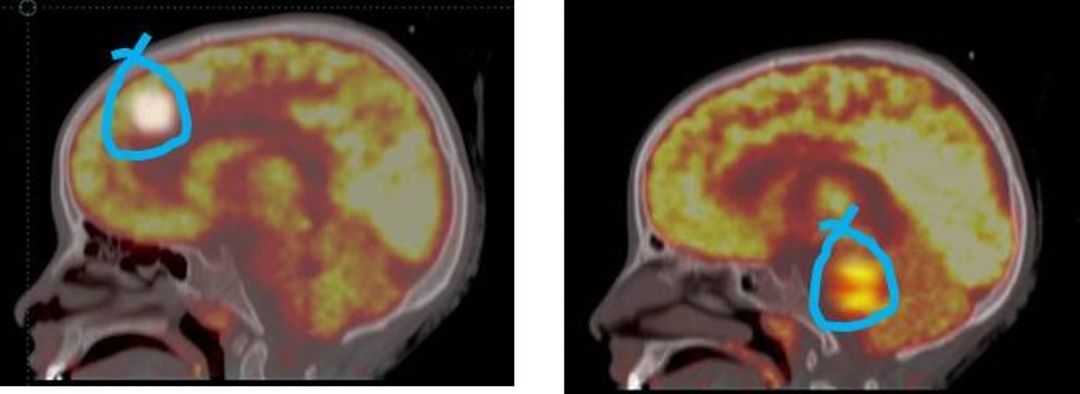

The study included 40 patients with median age of  5.6Yrs (range 4-16). of these 40, 24 (60%) had DO and 16 (40%) UD. In cases of detrusor overactivity TcPTNS decreased the activity in the mid-cingulate gyrus, hypothalamus, premotor cortex    and lateral pons (fig, 1a & b). These areas in brain are reported to be involved in the process of micturition.  On the contrary avid uptake was noted in lateral cingulate gyrus, mid pons and periaqueductal grey [PEG] in cases of underactive detrusor (UD) (fig. 2a). Hyper metabolism in these areas has been recorded during strong urge for micturition.

In the present study, in cases of overactive bladder TcPTNS decreased the activity in the mid-cingulate gyrus, hypothalamus, premotor cortex    [more on right side] and lateral pons. It is interesting to note that these are the areas which actually modulate in integrated manner during the process of bladder filling i.e. facilitate storage (Das Gupta et al., Jr Urol 2005, Laura et al., Continence 2024).

Figure 1 18 FDG PET showing decreased activity in the mid-cingulate gyrus, Hypothalamus, premotor cortex [more on right side] and Lateral pons